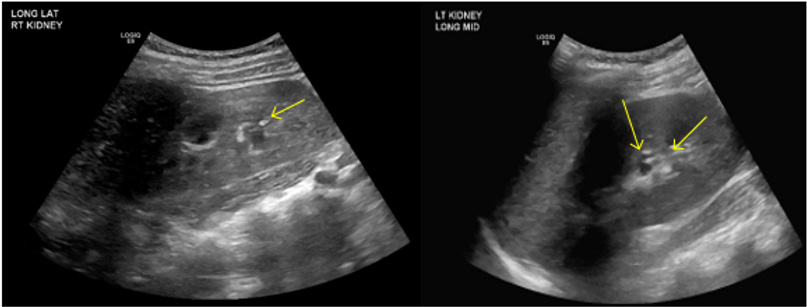

A few days later, blood work was performed at her primary pediatrician’s office, prompting admission for severe hypokalemia and a metabolic acidosis. Upon admission, laboratory findings included elevated ESR, anion gap 7 (plasma CO2 9 mmol/L, primary process with respiratory compensation), hypokalemia, serum creatinine 0.9 mg/dl, normocytic anemia, urine pH 7. Renal U/S revealed echogenic kidneys with punctate, echogenic non-shadowing foci in collecting system bilaterally, suggestive of nephrocalcinosis (Figure).